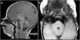

Large head in infant

Aqueductal stenosis

Calvarial thickening

Cerebral edema

Chiari II malformation

Communicating hydrocephalus

CSF overproduction

Dandy-Walker malformation

Intracranial cyst

Intracranial neoplasm

Macrocephaly

Noncommunicating hydrocephalus

Posterior fossa neoplasm